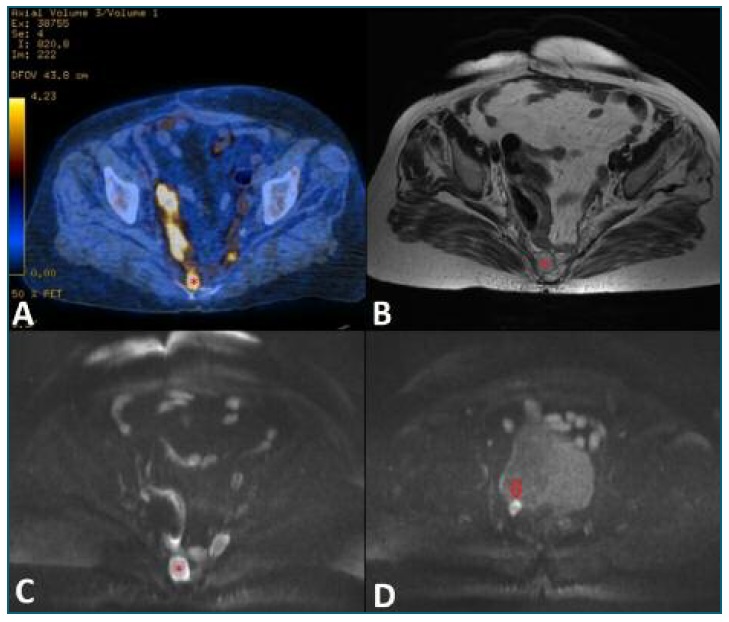

After surgery the patient was discharged and underwent adjuvant chemotherapy with Doxorubicin. Revaluation pelvic MRI two months after surgery revealed no signs of recurrence or residual disease. Four months later, one moth after chemotherapy ended, a Positron Emission Tomography - Computed Tomography (PET-CT) scan showed areas of increase uptake of 18F-FDG (fluorodeoxyglucose) in the presacral region (Figure 2 A), suggestive of active disease (peritoneal implants) and also in multiple lung nodules. Subsequent pelvic MRI confirmed the presence of two nodules anterior to the sacrococcygeal transition measuring 27 × 19 mm and 25 × 13 mm, and another one adjacent to posterolateral wall of the bladder with 14 × 10 mm, all of them showing restricted diffusion, suggestive of tumour recurrence (Figure 2 B-E). Given the pelvic recurrence and lung metastasis, patient resumed chemotherapy - Gemtacitabine and Docetaxel - with dose reduction after the first cycle due to pancytopenia and deterioration of liver and kidney function. After 3 cycles of chemotherapy PET-CT scan revealed increase in the number, size and metabolic activity of the previously described lesions. She underwent 4 cycles of another chemotherapy - Trabectedin. Soon after, she was admitted for diarrhoea with dehydration and reduction of urinary output. An abdominal ultrasound revealed two hypoechoic liver nodules consistent with metastasis and right hydronephrosis. A percutaneous nephrostomy was performed. A month later a head CT was performed due to altered state of consciousness, left hemiparesis and epileptic episode, revealing multiple brain metastasis. She passed away soon after being admitted in a palliate care unit.

Figure 2 PET-CT scan (A) showing areas of increased uptake of FDG-F18 in the presacral region suggestive of active disease (*). On T2-weighted axial MR image (B) the nodule is hypointense (*) and exhibit significant restriction of diffusion on diffusion-weighted axial MR image (C), suggestive of tumour recurrence. Similar lesions were detected adjacent to posterolateral wall of the bladder (arrow at D).